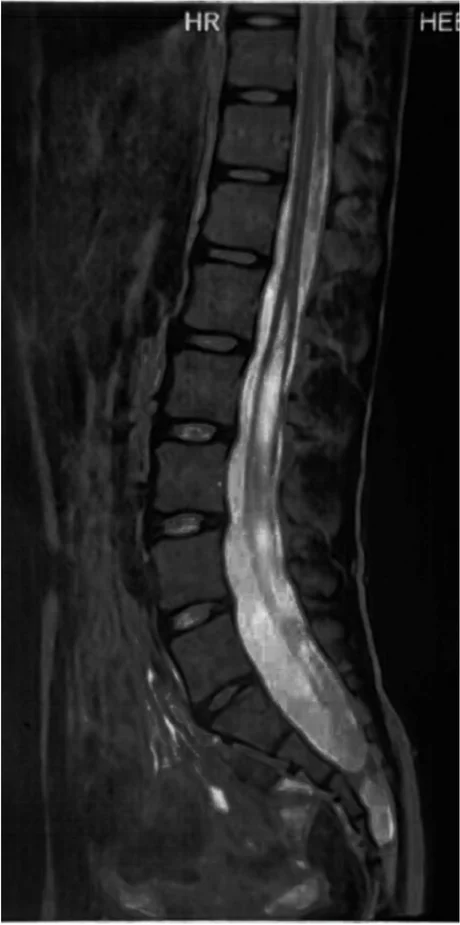

MRI – εξέταση κλειδί

• Συριγγομυελία: MRI αυχενικής/θωρακικής/οσφυϊκής μοίρας ανάλογα με την επέκταση και συχνά MRI εγκεφάλου/κρανιοαυχενικής συμβολής για έλεγχο δυσπλασίας Chiari ή άλλων συγγενών παθολογιών.

• Συρίγγιο άγνωστης αιτιολογίας: MRI με σκιαγραφικό για αποκλεισμό ενδομυελικού όγκου.

• Tethered cord: MRI θωρακο-οσφυϊκής μοίρας για εντόπιση του επιπέδου του μυελικού κώνου, απεικόνιση τελικού νηματίου για πιθανά λιπώδη στοιχεία ή άλλες συνοδές ανωμαλίες. Σε ειδικές περιπτώσεις, αξιολόγηση σε ύπτια/πρηνή θέση για έλεγχο κινητικότητας (κατά περίπτωση).